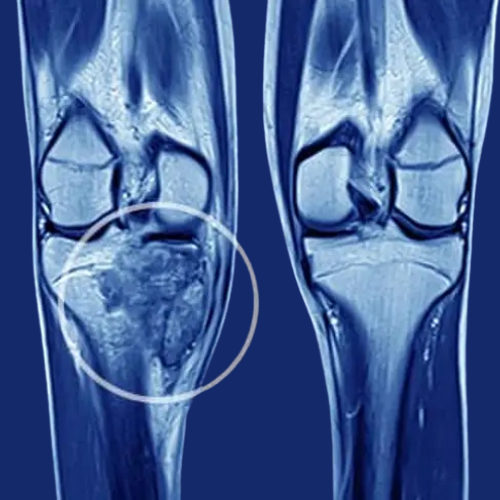

Giant Cell Tumour (GCT)

Aggressive benign tumour near joints; may cause swelling, pain, and fracture.

Treatment: Curettage with bone cementing, or resection with reconstruction.